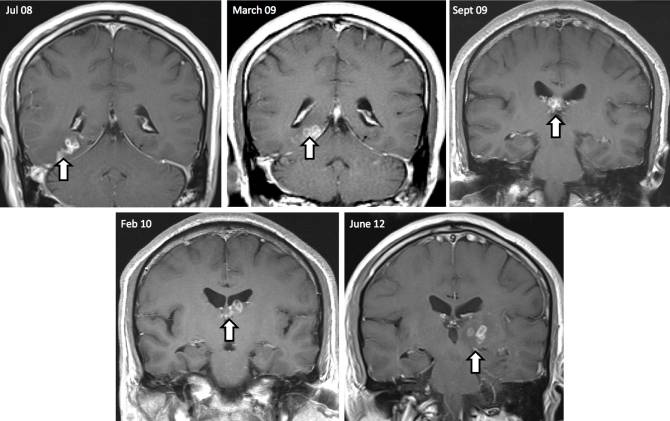

Un hombre de 50 años de etnia china fue ingresado en un hospital del Este de Inglaterra después de informar de síntomas de dolores de cabeza, olfato alterado, problemas de memoria y otros trastornos neurológicos. El paciente había vivido en el Reino Unido durante 20 años pero visitaba su patria natal a menudo. Después de dar negativo sobre varias enfermedades y no presentar ninguna otra anomalía, los médicos empezaron a hacer una serie de escaneos de su cerebro mediante resonancia magnética por imágenes. A lo largo de cuatro años, los médicos se dieron cuenta de una lesión que había migrado al menos 5 centímetros a través del cerebro, y después de efectuar una biopsia de su tálamo izquierdo, descubrieron una larva de gusano de 1 centímetro de largo. El paciente, cuya identidad no se ha dado a conocer, fue curado de su infección mediante una operación y está ahora recuperándose.

En el transcurso de cuatro años, el gusano migró 5 centímetros desde el lado derecho del cerebro al izquierdo, como se ve en esta sucesión de imágenes de las lesiones. (Foto: Hayley Bennett et al., Genome Biology 2014, 15: 510)